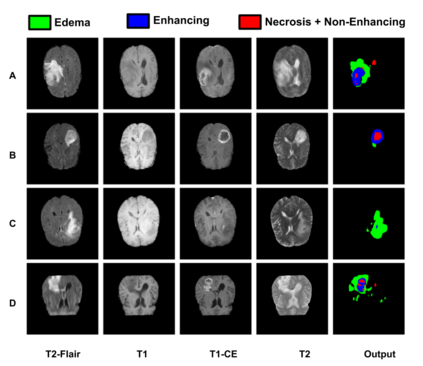

Gliomas are one of the most frequent brain tumors and are classified into high grade and low grade gliomas. The segmentation of various regions such as tumor core, enhancing tumor etc. plays an important role in determining severity and prognosis. Here, we have developed a multi-threshold model based on attention U-Net for identification of various regions of the tumor in magnetic resonance imaging (MRI). We propose a multi-path segmentation and built three separate models for the different regions of interest. The proposed model achieved mean Dice Coefficient of 0.59, 0.72, and 0.61 for enhancing tumor, whole tumor and tumor core respectively on the training dataset. The same model gave mean Dice Coefficient of 0.57, 0.73, and 0.61 on the validation dataset and 0.59, 0.72, and 0.57 on the test dataset.